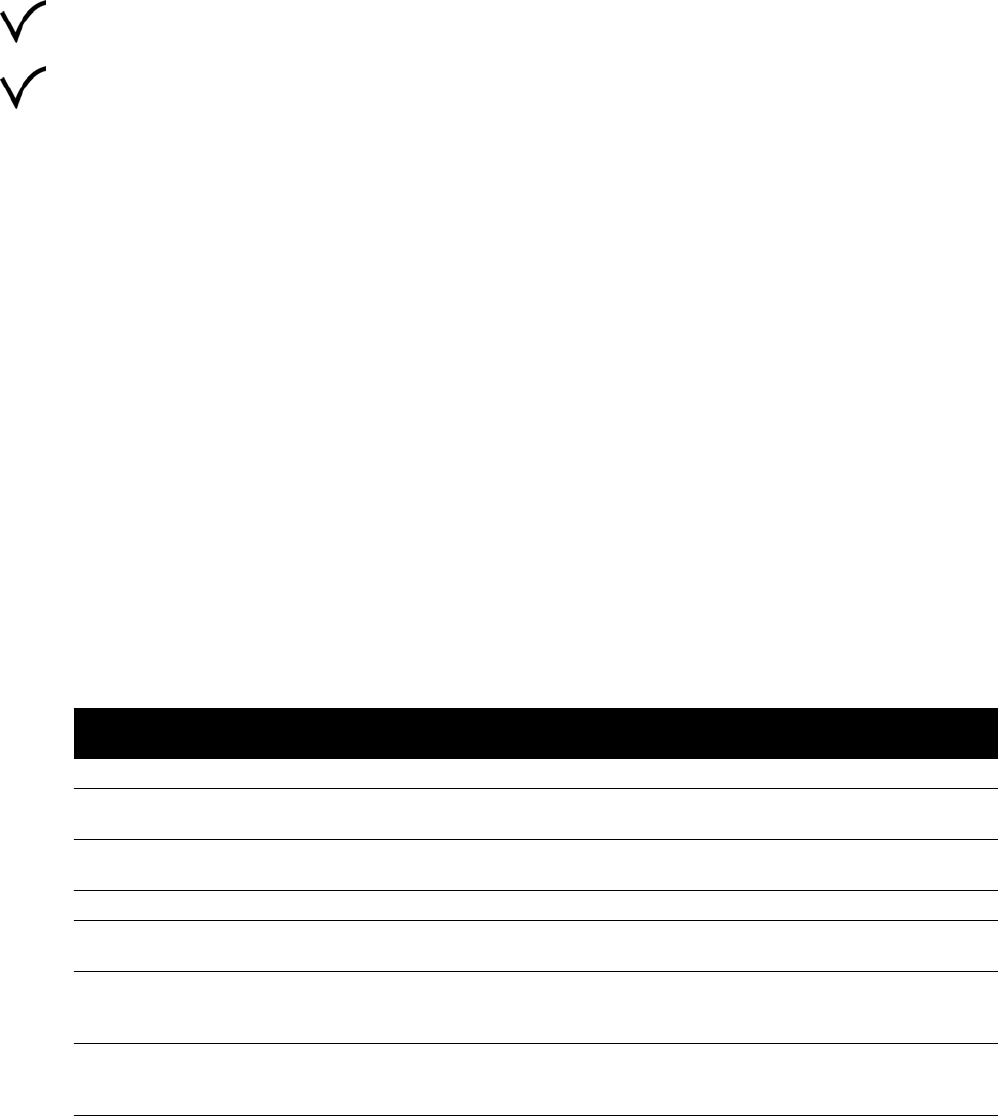

16.21.2 Mapy izokermy systemu C12/F12........................................................................ 310

16.21.3 Mapy izokermy systemu F15................................................................................ 311

16.21.4 Mapy izokermy systemu C20/F20........................................................................ 312